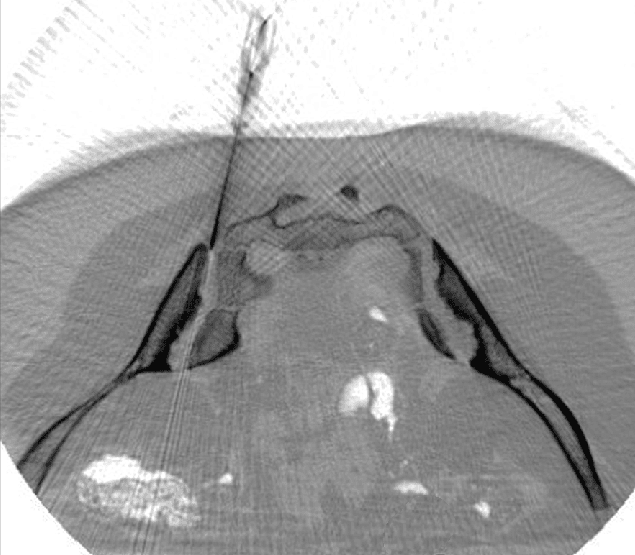

CT-assisted stem cell injection into joints

ANOVA IRM © Siemens Healthcare GmbH

Based on our specific diagnostics using arthro-MRI and non-radioactive contrast medium MRIs, we can, in contrast to many other clinics, deliver the stem cells with image support, e.g. using CT, precisely to the affected area. This means we can inject into and at the knee cavity as well as tendons/ligaments to specifically and quickly trigger an effect where inflammation causes pain. All interventions are performed under supervision and care of our anesthesiologist and are pain free.